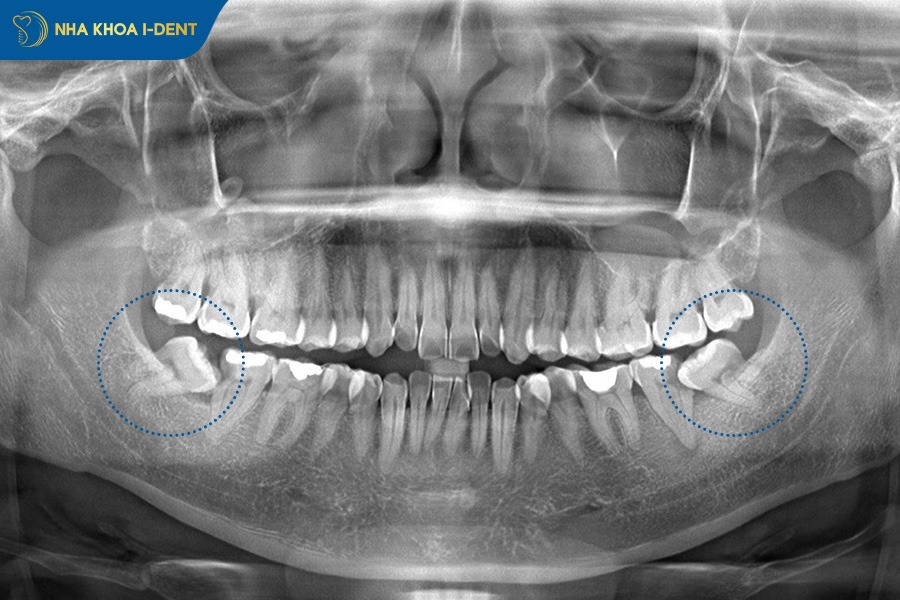

2.3. Răng khôn mọc ngầm hoặc mọc chen lấn

Răng khôn mọc ngầm, mọc lệch hoặc đâm ngang là một trong những yếu tố dễ khiến răng bị chạy lại sau khi tháo niềng. Khi răng khôn phát triển trong tình trạng thiếu khoảng trống sẽ tạo ra lực đẩy mạnh lên các răng phía trước. Lực đẩy này diễn ra âm thầm nhưng liên tục làm ảnh hưởng đến hướng dịch chuyển tự nhiên của răng và khiến những răng đã được sắp xếp thẳng hàng xô lệch trở lại.

Răng khôn mọc ngầm làm răng bị chạy lại sau khi tháo niềng.

3.4. Nhổ bỏ răng khôn mọc ngầm

Nếu răng chạy lại do răng khôn mọc ngầm gây áp lực lên răng hàm lớn và răng cửa thì bác sĩ sẽ chỉ định nhổ răng khôn để loại bỏ nguyên nhân làm chạy răng. Việc nhổ răng khôn càng sớm càng hạn chế tổn thương và ngăn tái phát chạy răng về sau. Sau khi nhổ răng khôn, bác sĩ sẽ đánh giá lại mức độ di răng và kết hợp đeo hàm duy trì để giữ răng ổn định trong quá trình xương hàm thích nghi.